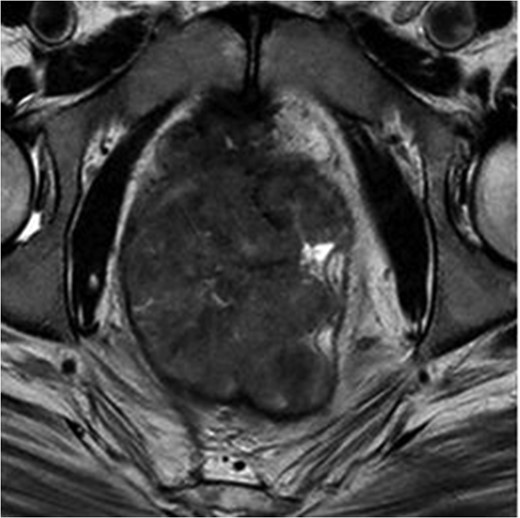

MRI pelvis large field T2 sagittal image through penile shaft showing the lesion involving the corpora cavernosum with extension in the spongiosum.